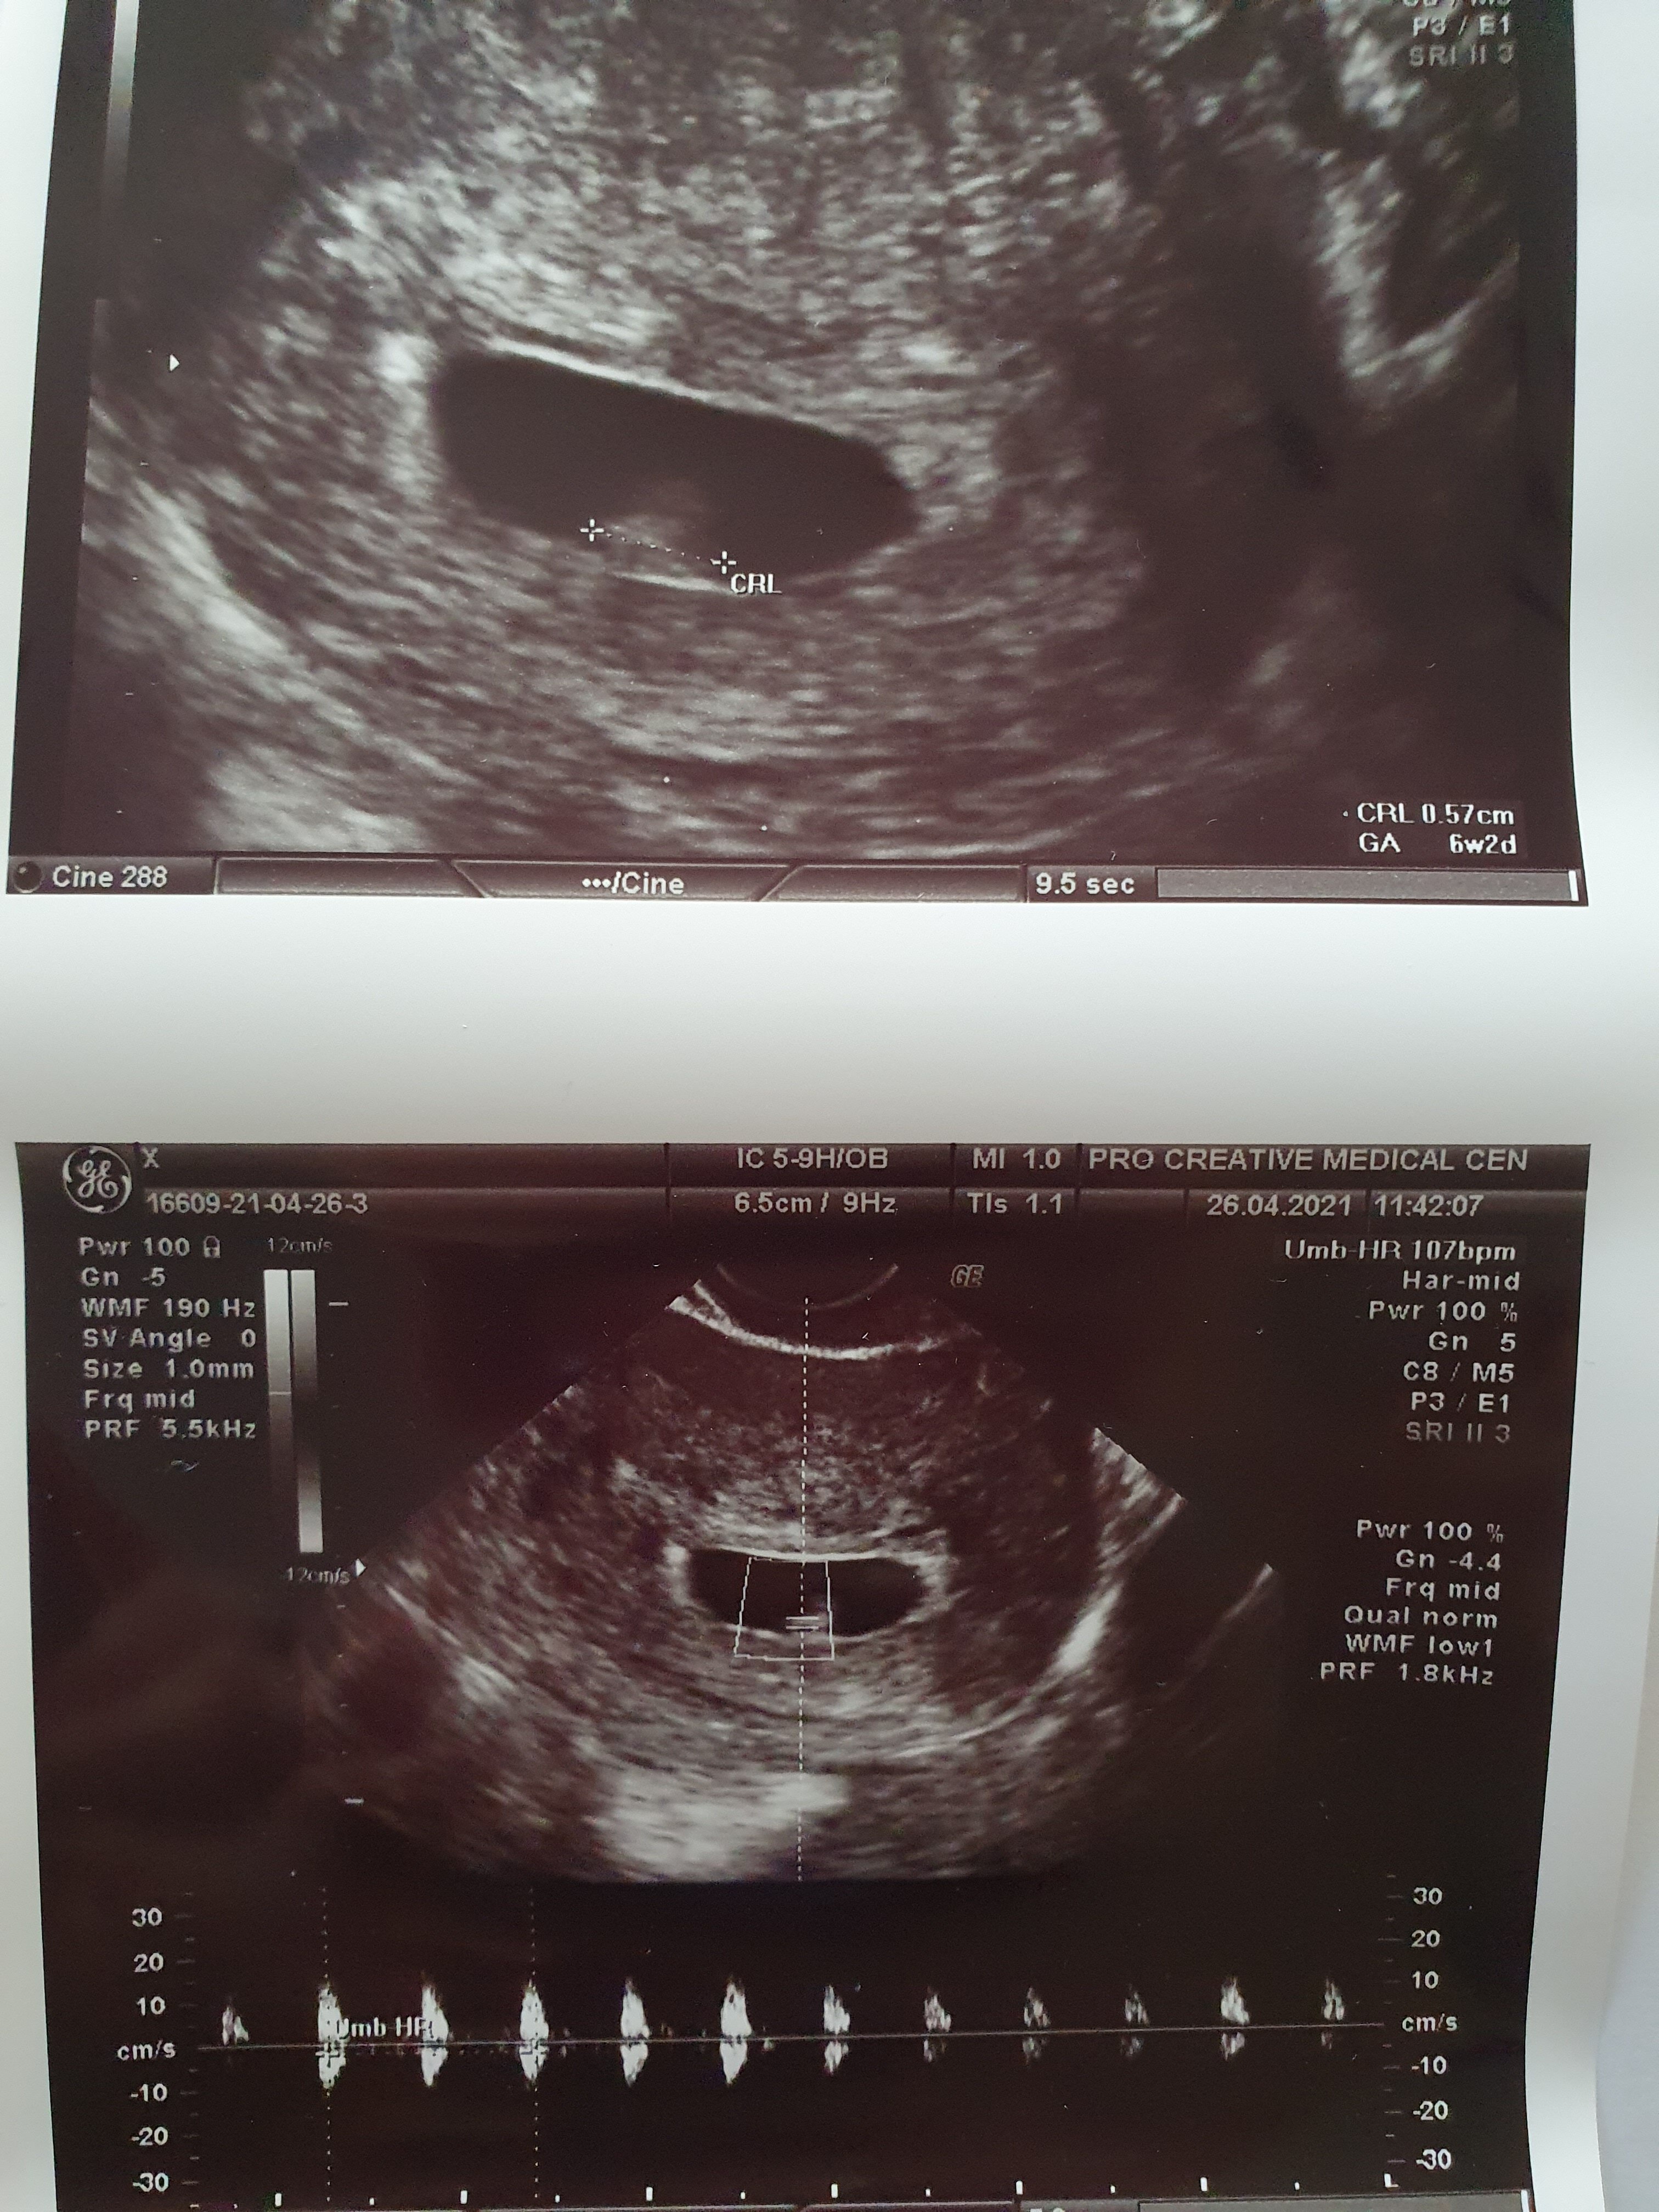

Już po wizycie. 🙂 Jest jeden zarodek w macicy, nie ma złego bliźniaka w jajniku. Idąc do lekarza miałam nadzieję na zobaczenie zarodka a usłyszałam serce i się popłakałam, poprzednia ciąża nie dotrwała do etapu serca. Lekarz mi gratulował a mnie zatkało, tylko wycierałam łzy szczęścia z kącików oczu. Torbiele w jajniku nie powiększają się. Zarodek ma 5,7mm, uderzenia serca 107/min. Kolejna wizyta za 2tygodnie, między 8 a 13 czerwca mam mieć badanie prenatalne i test Nifty. Zaproponował żebym zrobiła jeszcze jedna betę, ale powiedzialam, że wolę nie robić bo za bardzo mnie to stresuje. Termin porodu 19grudnia z zaleceniem wykonania cesarki. Wg pomiarów teraz jestem w 6+2.